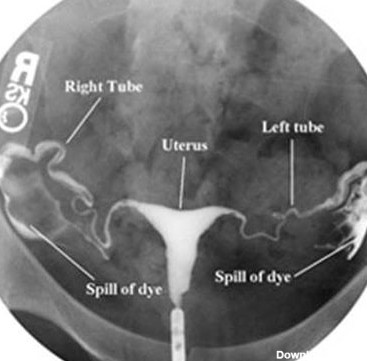

هزینه عکس رنگی از رحم یا هیستروسالپنگوگرافی (HSG)

عکس رنگی رحم چیست؟ مراحل، میزان هزینه و هرآنچه باید دانست